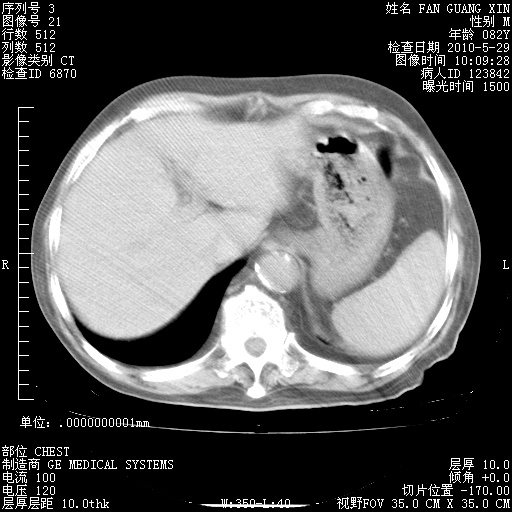

治疗3周后的肺部CT纵隔窗

再治疗10天后的肺部CT

再治疗10天后的肺部CT 纵膈窗

阅读此次胸部CT,肺间质渗出性改变较入院时有吸收。目前从体温、白细胞、中性分叶明显增高,肯定存在细菌感染(发生医院感染哦,若无消化道及泌尿系统等感染的依据,肺部感染可能大)。若你院头孢哌酮舒巴坦钠耐药率较高,同意你的方案,若48小时体温仍高,可考虑使用碳青霉稀类抗菌药物,同时可予超声雾化、注意滴数时加大液体量。白蛋白33.30g/L较低哦,需加强营养等支持治疗。